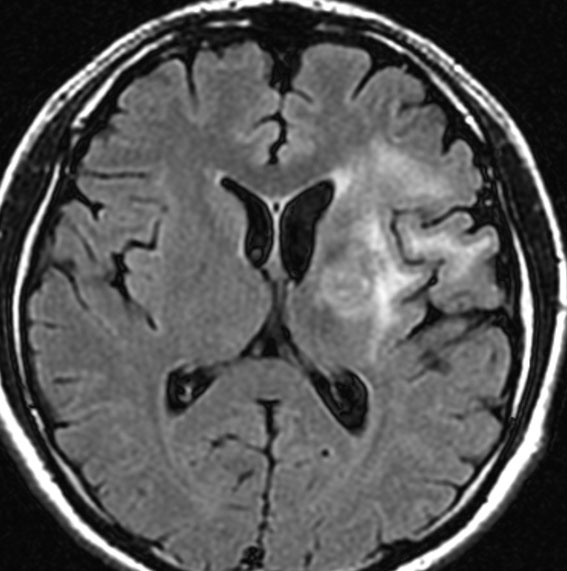

放射線治療後7週目

フレア画像です。腫瘍サイズが増大しています。もともと腫瘍周辺浮腫はなかったのですが大脳基底核と視床に浮腫が出現しています。スード・プログレッションの始まりです。

放射線治療後9週目

フレア画像です。たった2週間で脳浮腫が高度の脳浮腫となっています。失語症と右片麻痺と認知機能低下が生じました。ステロイド剤とグリセリンの点滴を行いました。